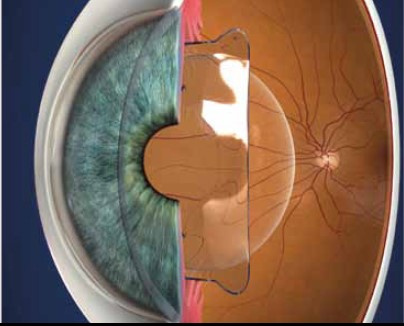

A Visian ICL é uma lente intraocular fácica de câmara posterior produzida pela Staar AG (Suiça). Trata-se de uma opção para a correção de graus de miopia inadequados para o laser, principalmente os graus elevados. A cirurgia é realizada sob anestesia tópica (colírio), sendo feita uma incisão pelo canto lateral da córnea para o implante da lente. Por se tratar de uma lente dobrável, na maioria dos casos não é necessária sutura para adequada cicatrização.